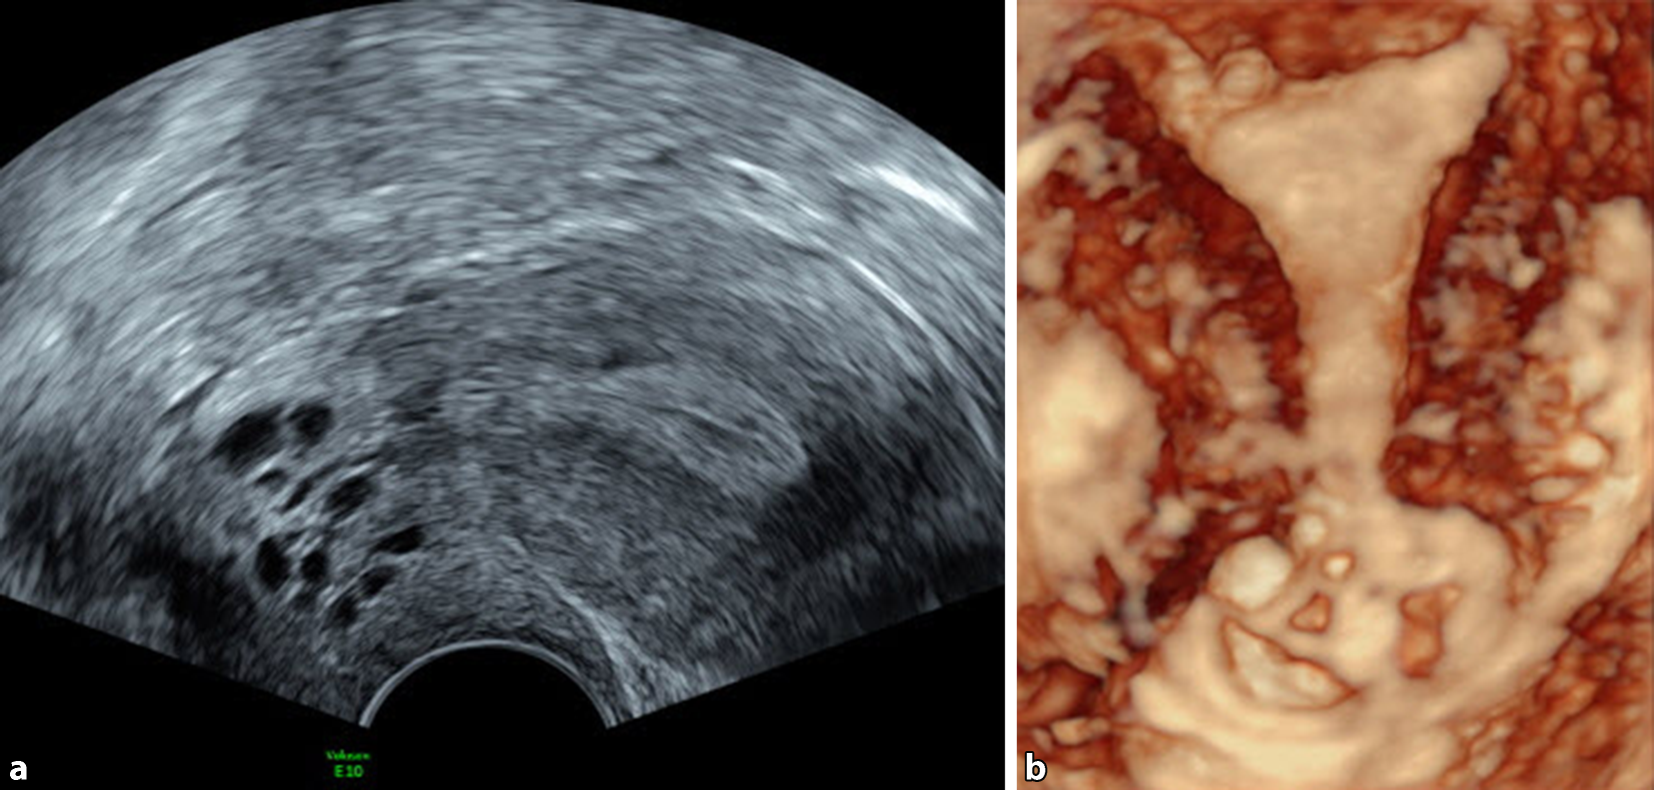

Ovula Nabothii liegen oft unmittelbar dem Portioepithel an, manchmal liegen sie auch „höher“, bis zum Bereich des unteren Uterinsegments (Abb. 1). Da Ovula Nabothii einen echoarmen Inhalt haben, beobachten wir oft unmittelbar dahinter eine dorsale (distale) Schallverstärkung (Abb. 2). Schallverstärkung wird in manchen Anwendungsbereichen des Ultraschalls (Gallenblasendiagnostik, Mammasonografie) als diagnostisches Kriterium bei der Beurteilung von zystischen Strukturen herangezogen. Die erhöhte Echodensität hinter dem Ovulum Nabothii muss als Schallartefakt erkannt werden und darf nicht als Strukturverdichtung des Zervixgewebes interpretiert werden (Abb. 3). Ovula Nabothii sind selten bei nulliparen Frauen, sie treten nach Geburten, Operationen an der Zervix, wie z. B. der Versorgung von Emmet-Rissen, oder auch nach Konisationen auf. Ovula Nabothii können platzen und der Inhalt ausrinnen, in diesem Bereich können sich neue Zysten, aber auch echodense Narbenstränge bilden. Im Ultraschall sind Ovula Nabothii ein gutes Einsatzgebiet für den 3D-Schall: Dieser, hilft die Zyste besser zu lokalisieren (Abb. 4, 5 und 6).

Abb. 5

a Multiple Ovula Nabothii im B‑Modus und b im 3D-Modus